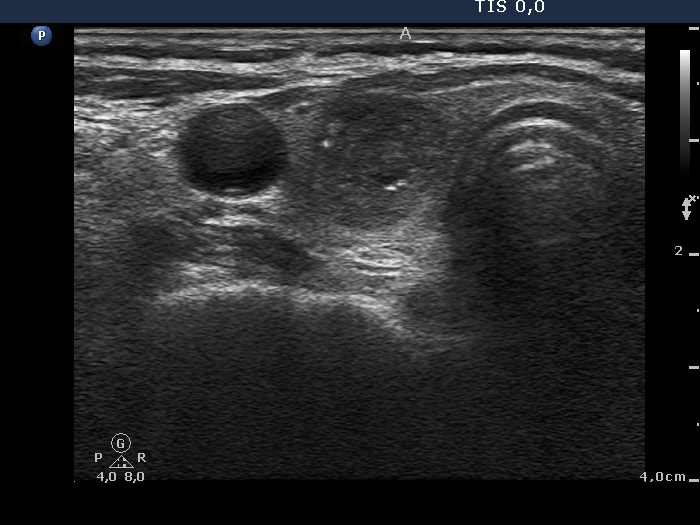

|

Papillary carcinoma (histological diagnosis) - case conp 035 |

The thyroid presented in the left images is composed of moderately hypoechogenic and hypoechogenic nodules, while the lobe in the malignant case is diffusely hypoechogenic and has a less hypoechogenic but more inhomogeneous lesion in its dorsal part. Both the left thyroid and the malignant nodule in the right images have hyperechogenic granules and lines which correspond to a connective tissue.